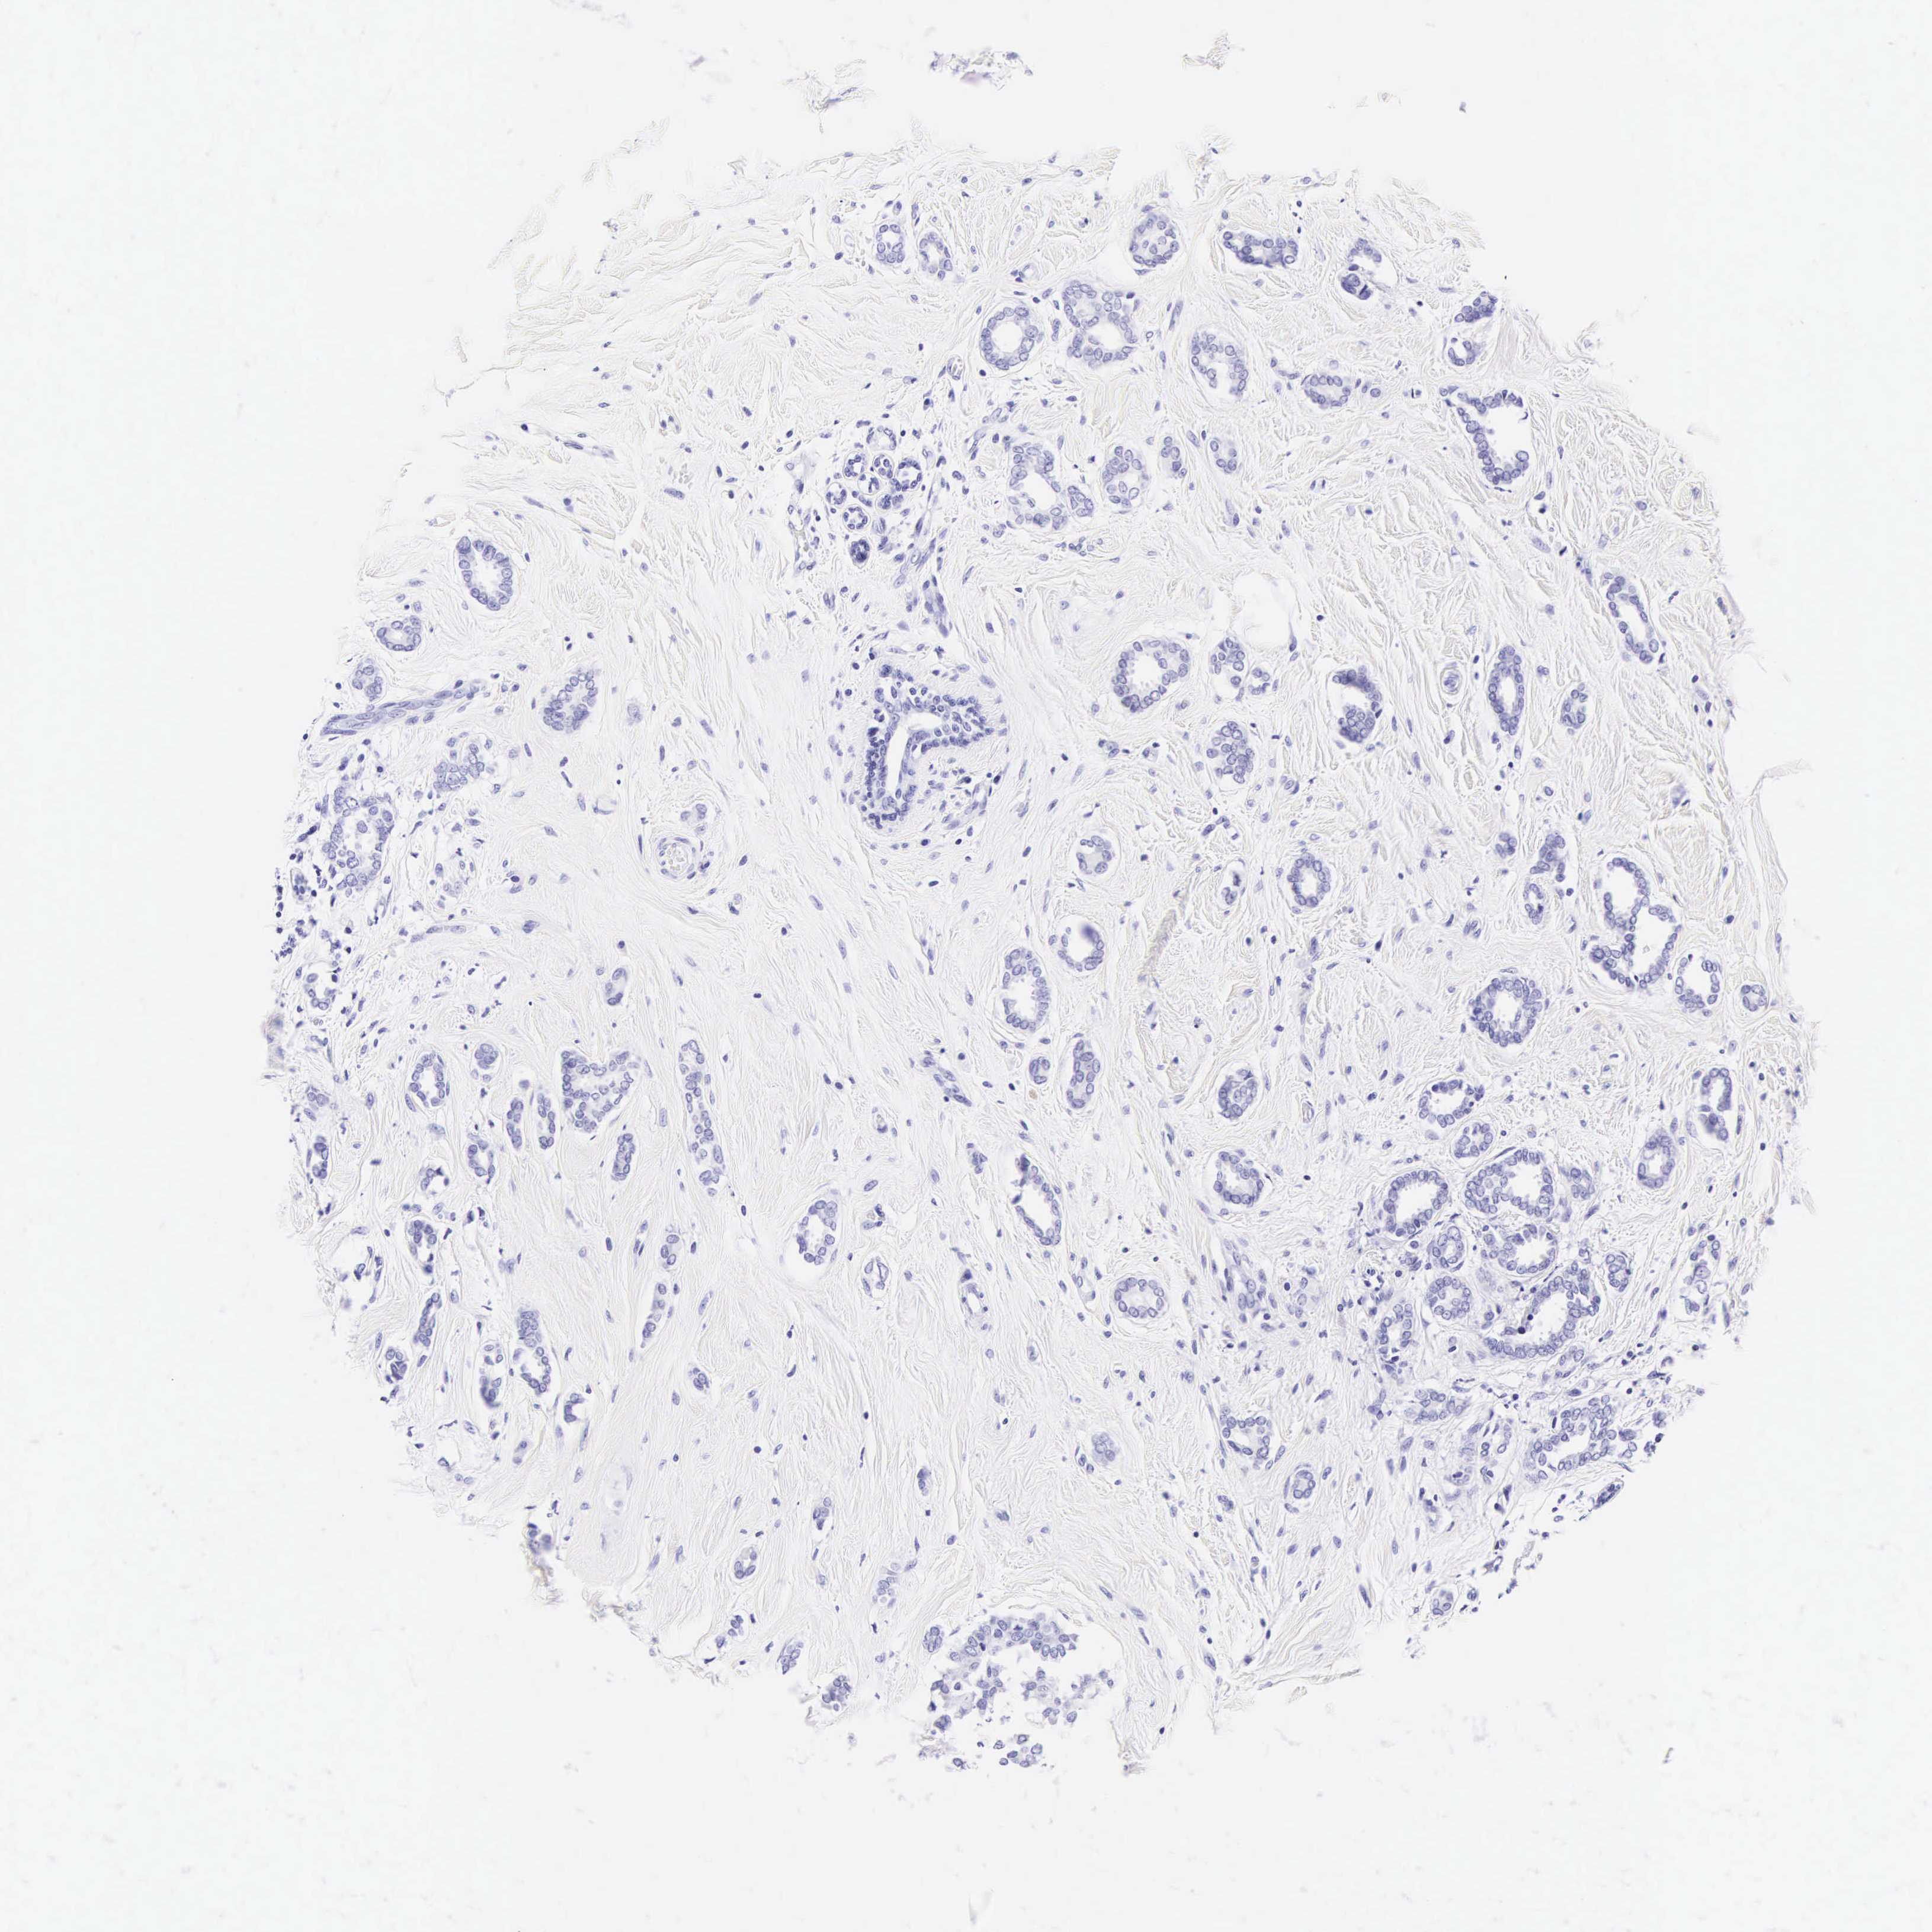

Breast cancer

Human cancer